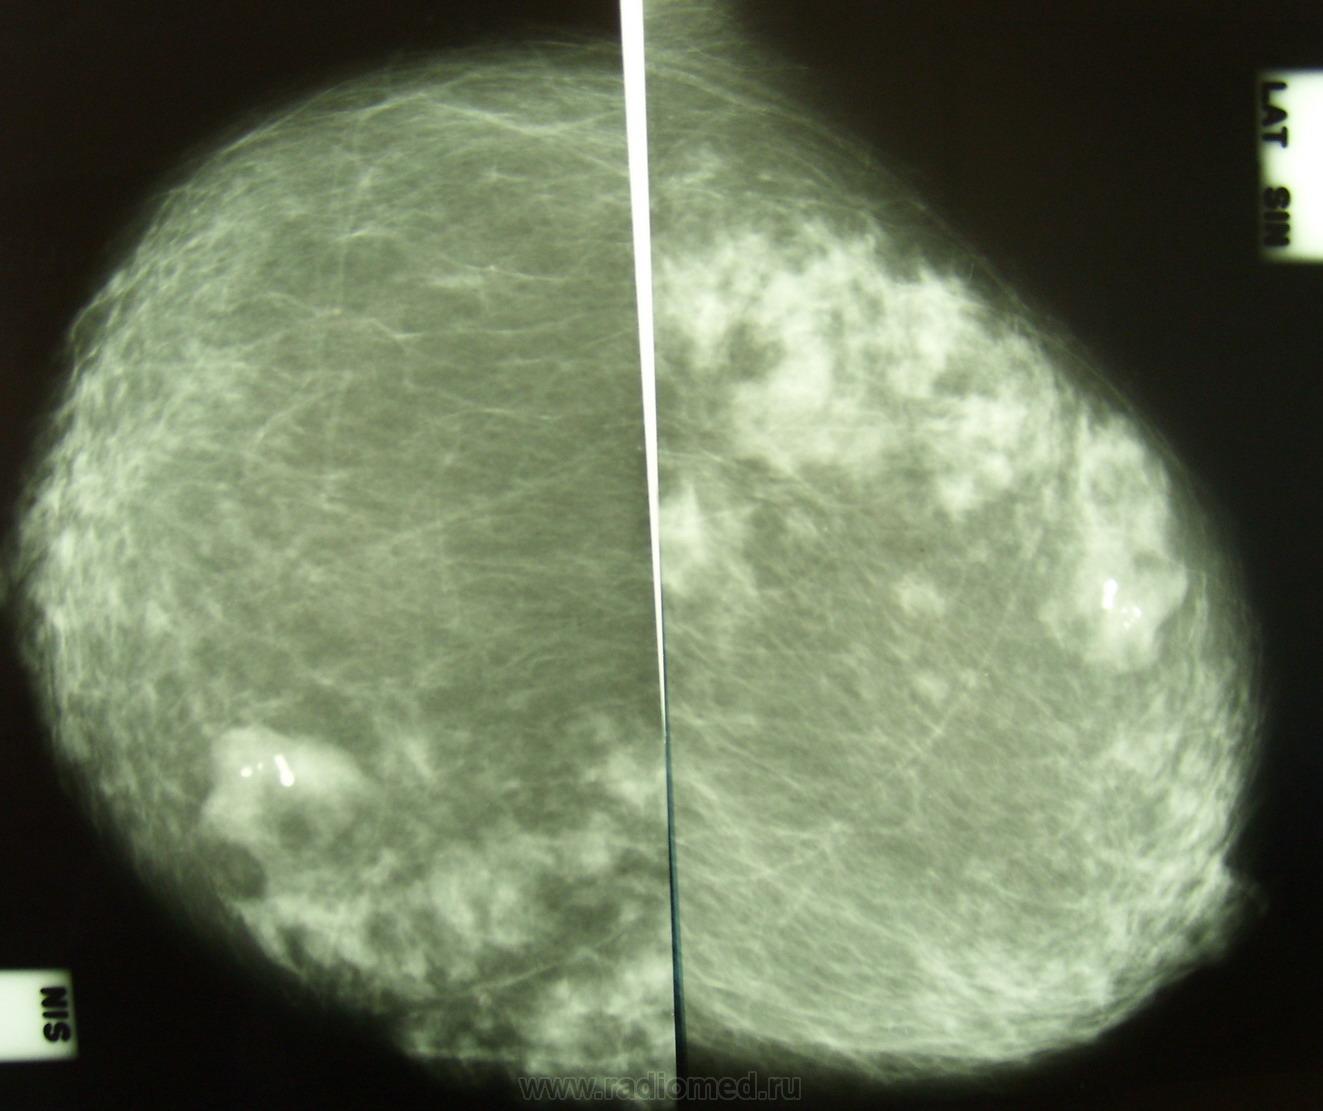

УЗИ молочных желез — информативный и безопасный метод диагностики, с помощью которого можно точно оценить состояние желез, обнаружить доброкачественные и злокачественные образования, уточнить диагноз. Это доступное по цене исследование безвредно и не несет лучевой нагрузки. Оно имеет большое значение в ранней диагностике заболеваний и нередко применяется в профилактических целях. На УЗИ может направить маммолог, онколог, эндокринолог, гинеколог.

Сделать УЗИ молочных желез можно в качестве первичной диагностики и для уточнения уже предполагаемого диагноза. Метод основывается на способности высокочастотных ультразвуковых волн с различной скоростью отражаться от тканей с разной плотностью.

С помощью ультразвуковой диагностики можно обнаружить следующие заболевания:

- воспалительные заболевания — мастит, абсцессы, лактостаз у кормящих женщин, мастопатии различного происхождения и типа — фиброзно-кистозные, диффузные и пр.;

- врожденные аномалии молочной железы;

- рак;

- кисты и доброкачественные опухоли;

кальцинаты.

Для оценки кровотока в тканях молочных желез используется доплерография. Данные, полученные в результате биопсии под контролем УЗ-аппарата, могут сказать о природе и характере образований в молочных железах.

Кому противопоказано

УЗИ практически не имеет противопоказаний. Однако важно отметить, что информативность обследования груди таким способом у женщин молодого возраста выше, поскольку ткани молочных желез с возрастом становятся более рыхлыми. Поэтому после 40 лет УЗИ в большинстве случаев сочетается с рентген-диагностикой (маммографией).